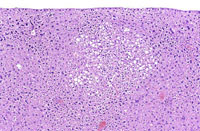

A large eosinophilic focus of cellular alteration that has a well demarcated border. Hepatocytes comprising eosinophilic foci typically have an increased cytoplasm that stains more eosinophilic than the cytoplasm of surrounding hepatocytes. If the hepatocytes within an eosinophilic focus are sufficiently large and numerous, there may be evidence of slight compression of normal hepatic parenchyma along a portion of the border of the focus.

An eosinophilic focus of cellular alteration with slight protrusion above the normal surface contour of the liver.